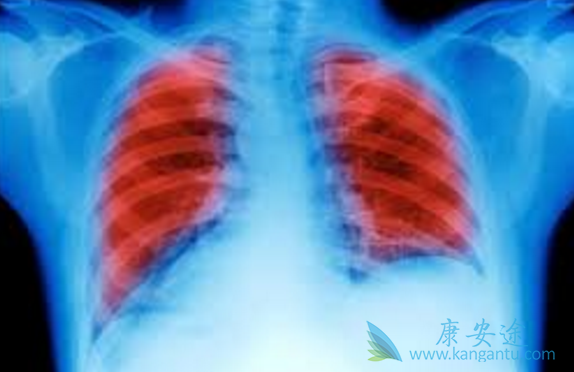

检查发现小细胞肺癌中晚期能活多久?

近年来,肺癌不再是老年人的专利,越来越多的年轻人也加入了肺癌的行列,甚至是不吸烟的年轻人。因早期肺癌大都无明显症状,有些患者甚至没有症状,导致很多人发现时已是中晚期。那么,肺癌晚期有多可怕?肺癌晚期临终前症状往往比较明显,常见的临终前症状有声嘶、胸痛、气促、发热、咳血等,给患者带来了很大的痛苦。那肺癌中晚期能活多久

一旦被诊断为“肺癌晚期”,很多患者都陷入了无限的恐慌中,感觉死神即将到来。据统计,在肺癌的治疗中,超过70%的肺癌患者因没及时发现病情,导致晚期肺癌不能手术治疗。以肺癌第IV期为代表,若不及时治疗生存期大约在3-6个月。其实,肺癌晚期患者还能活多久并非一概而论。肺癌晚期患者只要积极治疗,也是能延长生存期的。

肺癌主要分为非小细胞肺癌和小细胞肺癌。非小细胞肺癌在术后发生复发转移的几率也比较高,手术后五年的非小细胞肺癌患者存活率分别:第I期为44.5%,第II期为36.1%,少部分第III A期则少于30%,越早治疗肺癌,患者的存活率就越高。而对于早期的小细胞肺癌患者来说,若是及时以手术切除联合生物治疗、放化疗,在没有肺癌淋巴转移的情形下,三年的存活率可达65%,五年存活率可达50%。